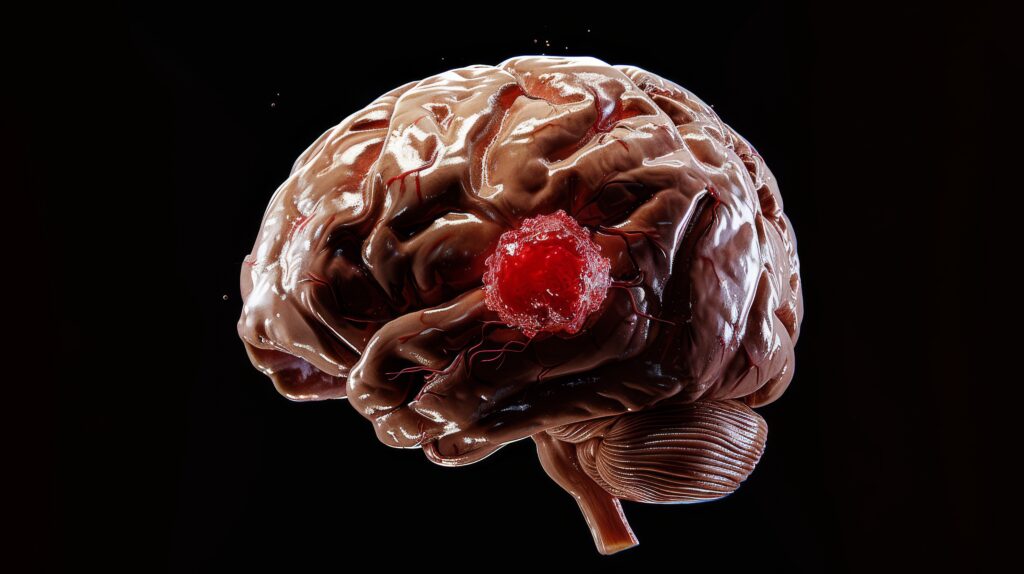

Understanding Brain Tumours: Patient Education and Awareness

What Are Brain Tumours?

Brain tumours are abnormal growths of cells within the brain or surrounding tissues. They can be benign (non-cancerous) or malignant (cancerous). Brain tumours can affect brain function by pressing on nearby areas or by interfering with normal brain processes.